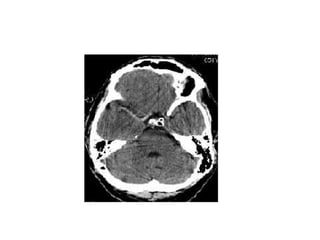

When stroke-related edema is extensive and life-

threatening, it is sometimes called malignant brain

edema.

Life-threatening brain edema that is associated with

stroke occurs most commonly in patients with

extensive ischemia in the temtory of a middle

cerebral artery (MCA).